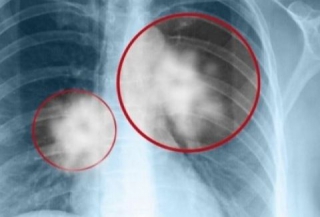

Στο Κέντρο Μοριακής Ανοσολογίας (CIM) στην Κούβα διατίθεται δωρεάν, το πρώτο εμβόλιο στους ασθενείς με καρκίνο του πνεύμονα. Σύμφωνα με τους ειδικούς είναι μια νέα θεραπεία, μοναδική στον κόσμο, η οποία μπορεί να σταματήσει την εξέλιξη της νόσου, χωρίς να επηρεάζει την ποιότητα ζωής των ανθρώπων.

«Τα αποτελέσματα του εμβολίου δίνουν ένα ποσοστό επιβίωσης των ασθενών, ο όγκος δεν εξαλείφεται, αλλά σταματά να αναπτύσσεται, επιτρέποντας στους ασθενείς να ζουν περισσότερο και ιδιαίτερα με μια καλή ποιότητα ζωής, οι παρενέργειες είναι ελάχιστες», λέει η γιατρός Arlhee Diaz.

Το εμβόλιο θα μπορούσε να διατεθεί και σε άλλες χώρες αλλά λόγω του αποκλεισμού από τις ΗΠΑ προς το παρόν είναι ανέφικτο. Το μόνο που μπορεί να επιτευχθεί είναι η εγγραφή σε μια βάση δεδομένων ώστε να γίνει ανταλλαγή απόψεων για την θεραπεία της νόσου. Οι Κουβανοί έχουν πρόσβαση μέσω του εθνικού συστήματος υγείας της χώρας τους ενώ οι αλλοδαποί πληρώνοντας ένα συμβολικό πόσο.

Το Κέντρο Μοριακής Ανοσολογίας στην Κούβα εστιάζει τις εργασίες του για την έρευνα και την παραγωγή φαρμάκων κατά του καρκίνου, την κύρια αιτία θανάτου μεταξύ των Κουβανών. Οι έρευνες ξεκίνησαν το 1994 με την παραγωγή μονοκλωνικών αντισωμάτων.